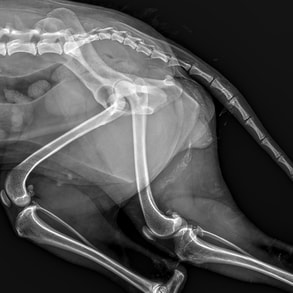

Breathing Difficulties

Increased respiratory effort

Increased respiratory rate

Pale or blue gums

Loss of appetite and lethargy

Trauma

Limping

In pain and vocalising

Bleeding